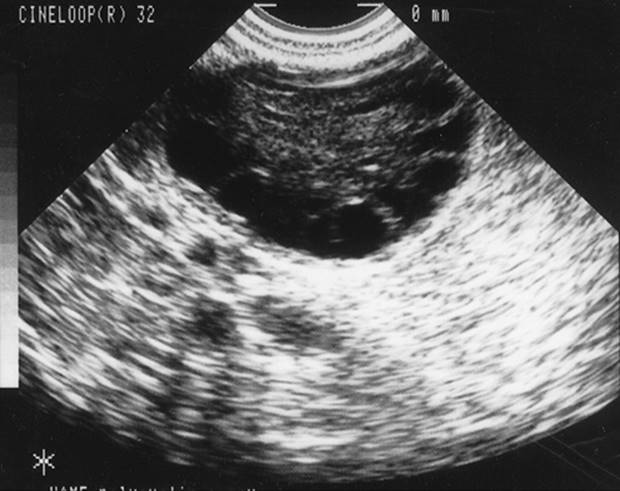

Other diagnostic criteria for PCOS have been proposed, including the finding of a polycystic ovary morphology on ultrasound, with multiple 2-to 8-mm subcapsular preantral follicles forming a “black pearl necklace” sign (Fig. 37.5). However, it should be noted that “polycystic ovaries” on sonography or at pathology are simply a sign of androgen excess and possibly PCOS. For example, this ovarian morphology is frequently seen in patients with adrenal hyperplasia (Table 37.2), and up to 25% of unselected women have polycystic ovaries on ultrasound, many of which are normoandrogenic with regular menstrual cycles. Hence, we consider the appearance of polycystic ovaries, particularly on sonographic exam, to be a sign, albeit nondiagnostic, of androgen excess and PCOS.

FIG. 37.5. Transvaginal ultrasound visualization of a polycystic ovary. Note the string of subcapsular follicles measuring 2 to 8 mm in diameter, with increased central stromal mass.

Approximately 70% to 80% of women with PCOS demonstrate frank elevations in circulating androgens, particularly free testosterone, and 25% to 50% will have elevated levels of the adrenal androgen metabolite, DHEA-S. Prolactin levels are usually normal, although they may be slightly elevated (generally <40 ng/mL) in a small fraction of patients. The luteinizing hormone/follicle-stimulating hormone (LH/FSH) ratio is greater than 2 or 3 to 1 in approximately 60% of these patients. As noted, the ovaries of about 70% of patients with PCOS usually contain intermediate and atretic follicles measuring 2 to 8 mm in diameter, resulting in a “polycystic appearance” at sonography (see Fig. 37.4, Fig. 37.5). About 60% of patients with PCOS are obese, although significant fractions are nonobese.